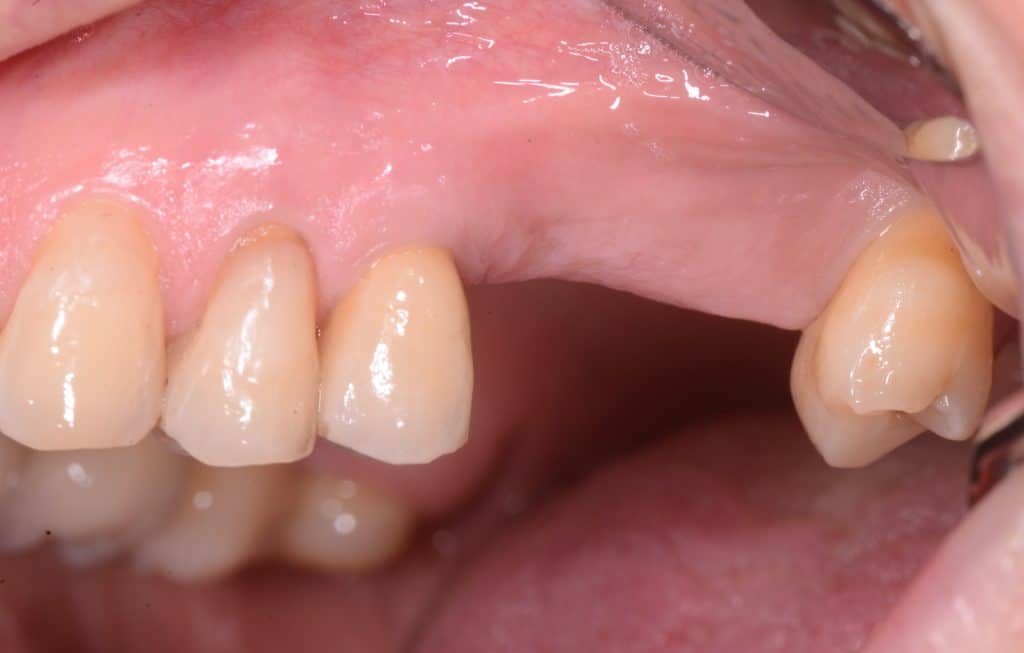

operating area, occlusal view

operating area, lateral view